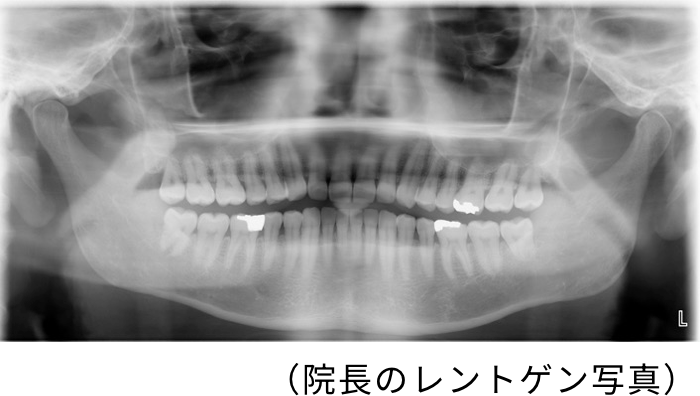

野島院長には虫歯(治療済み)が何本あるでしょう? 上のレントゲン写真を見て考えてみてくださいね。

3本(銀歯やインプラント、詰め物などは、透明感のない白色に写ります。)